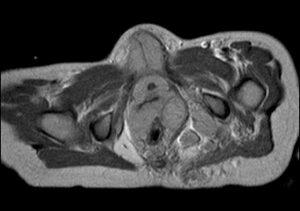

Gli esami ematochimici di routine sono normali, alcuni indici tumorali (alfa-feto-proteina, beta-HCG, NSE) risultano negativi, mentre la RMN dell'addome, oltre a tessuto endopelvico che circonda l'utero, l'uretra e le pareti del retto, documenta noduli multipli, da pochi mm a 3 cm, all'emergenza e lungo il decorso di plessi e radici nervose sacrali, soprattutto a sinistra, nodulazioni nella muscolatura glutea e nel muscolo otturatore interno di sinistra e piccoli noduli plurimi lungo il decorso del nervo sciatico di sinistra (Figura, vedi a lato).